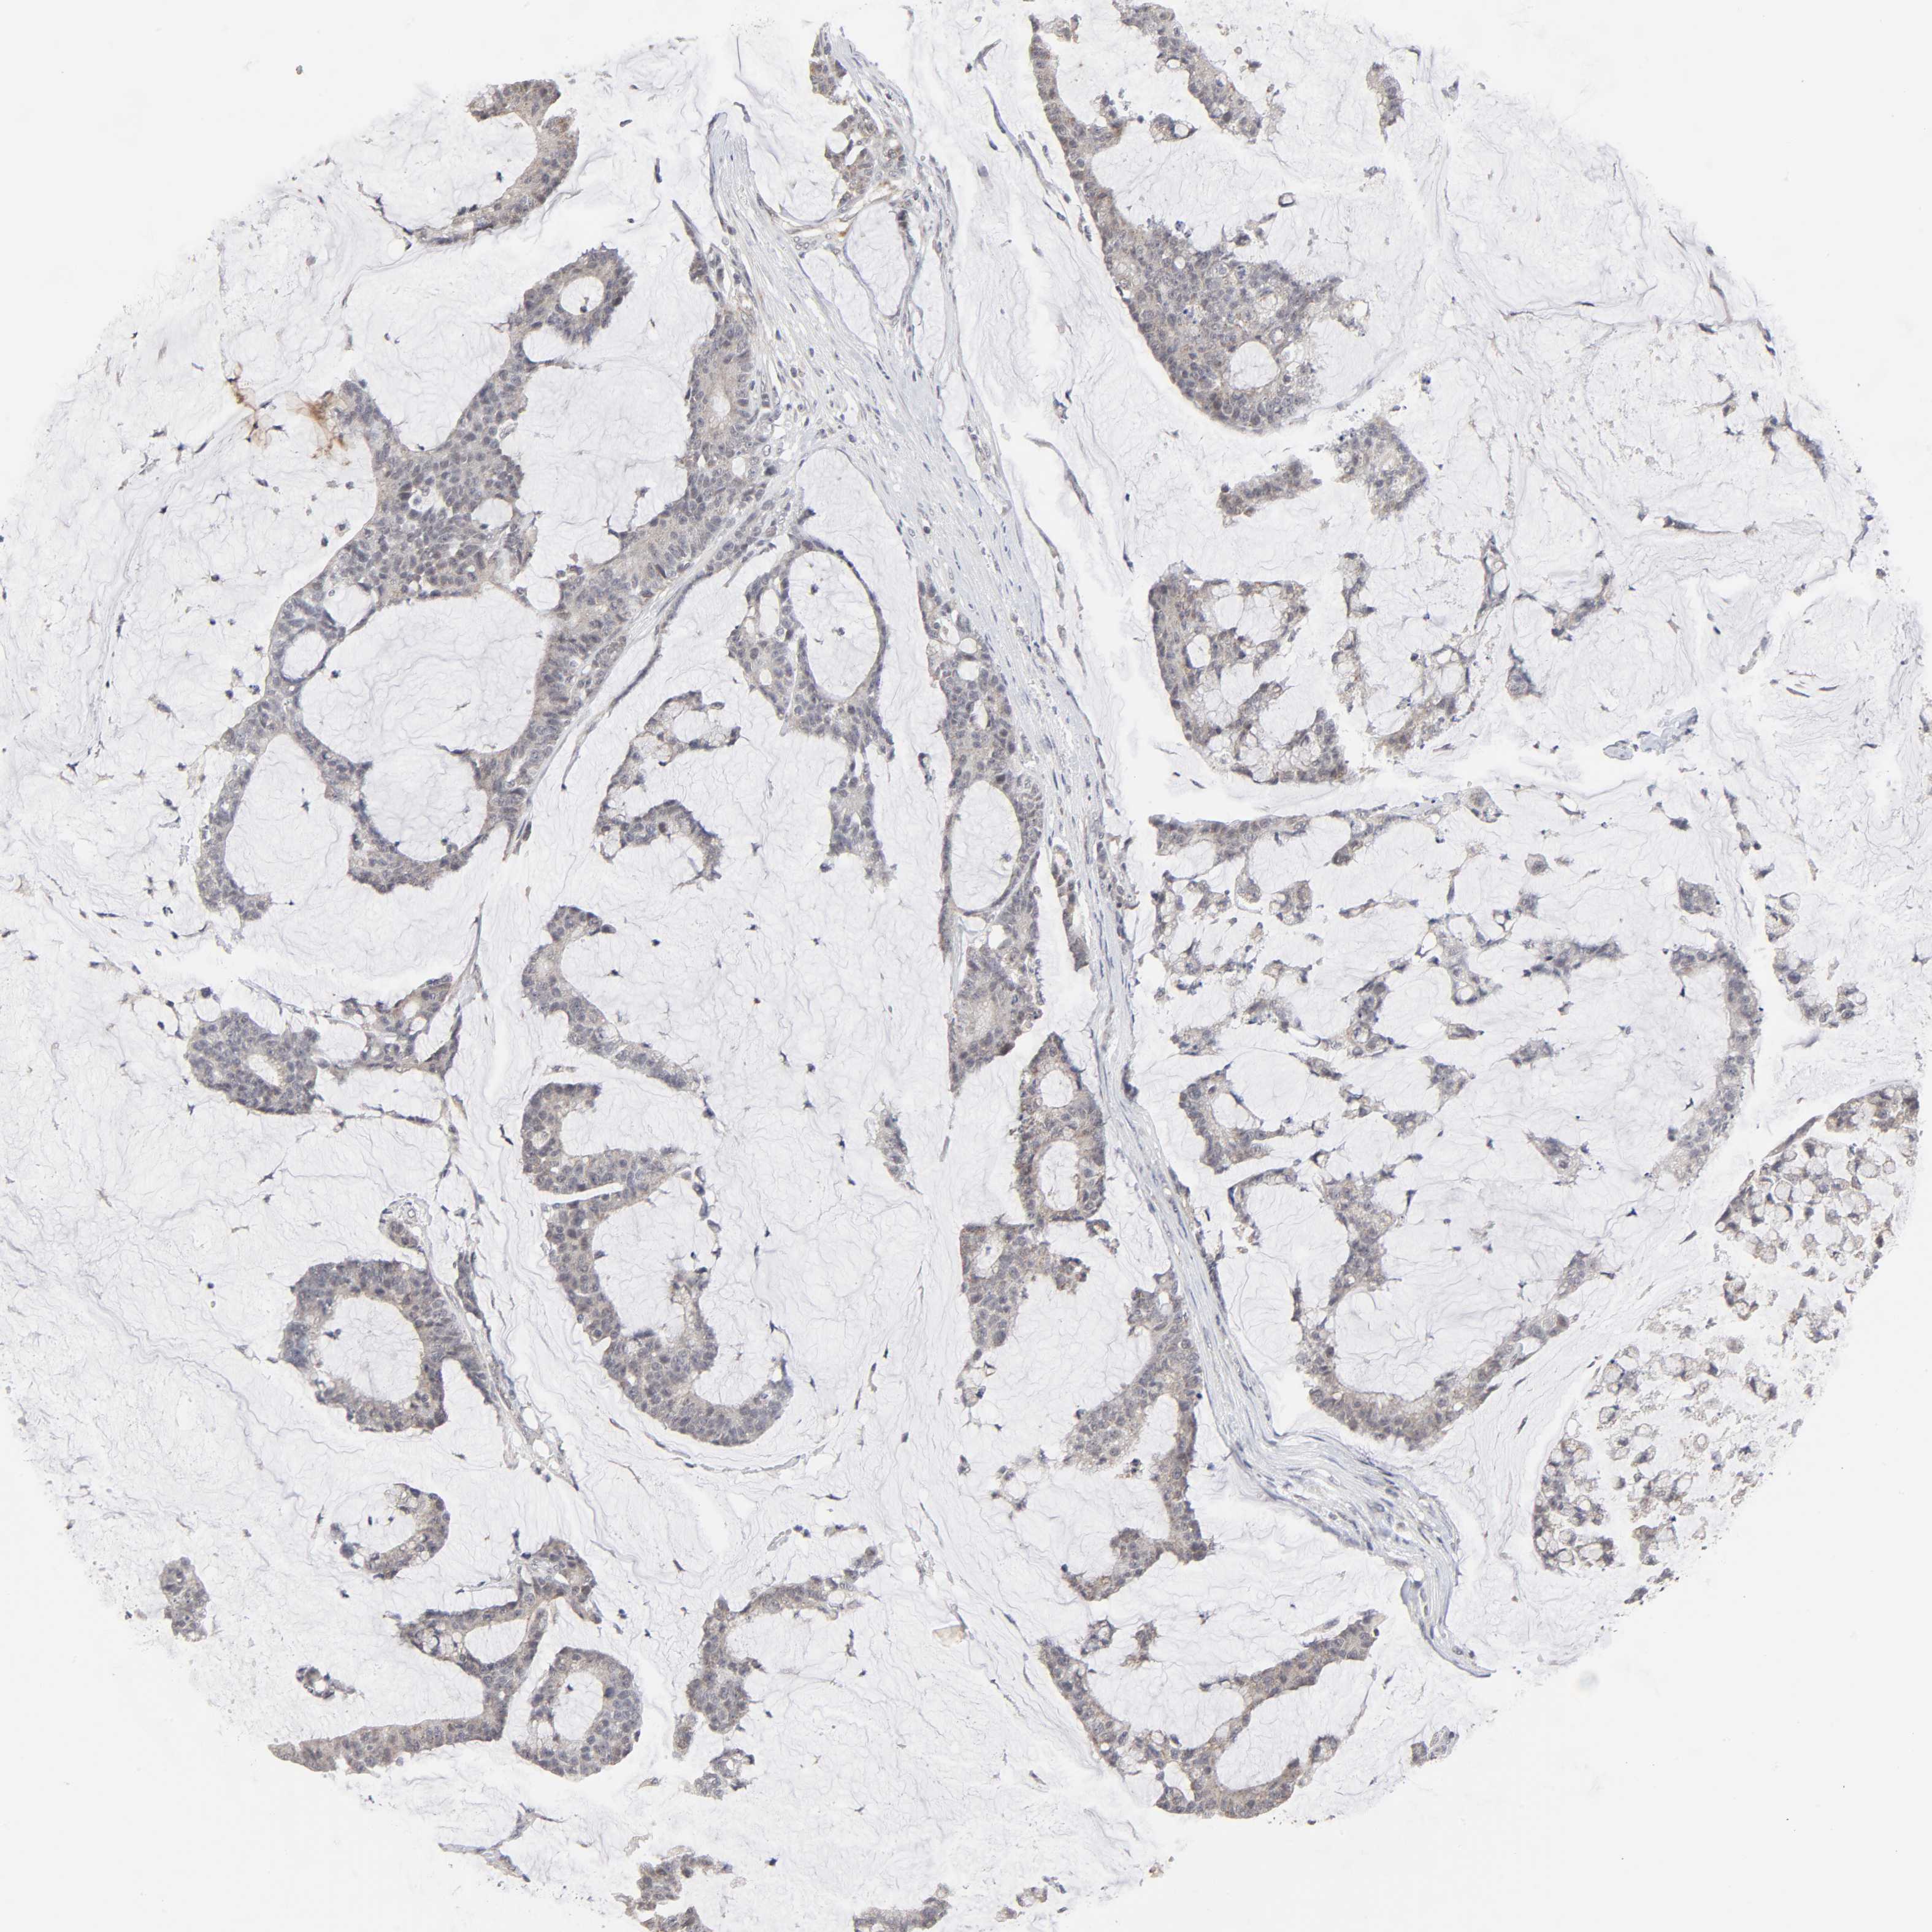

CANCER COLORECTAL CANCER Show tissue menu

Colorectal cancer

Human cancer

Colon adenocarcinoma